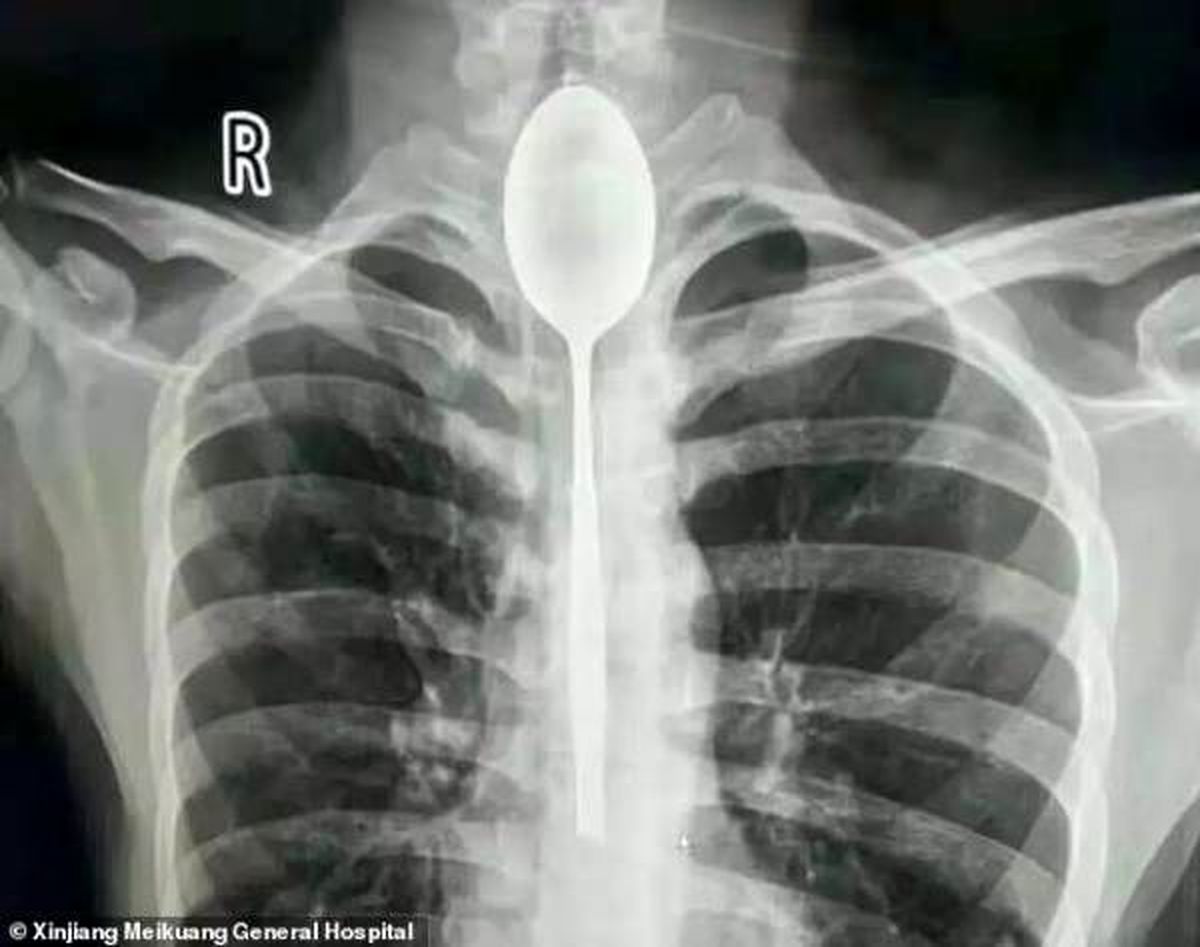

دردسر یک شرط بندی عجیب /قاشق 20 سانتی یکسال در گلوی مرد !+ عکس

مرد چینی در یک شرط بندی احمقانه قاشق 20 سانتی را بلعید و از آنجایی که مشکلی در خوردن و آشامیدن نداشت تا یکسال این قاشق داخل گلوی وی ماند.

مرد چینی قاشق فلزی 8 اینچی را به عنوان یک شیرین کاری احمقانه در سال گذشته بلعید. قاشق در مری او گیر کرد، اما چون به راحتی می توانست بخورد و بنوشد، هرگز به دنبال کمک پزشکی برای بیرون آوردن آن نبود. او می گوید تنها چند روز پیش به علت ضربه وارد شده به قفسه سینه ، دچار درد قفسه سینه شد.

مردی که نامش فاش نشده است از منطقه جین جیانگ چین به پزشکان گفت :او یک قاشق فولادی ضد زنگ را در طی یک شرط درحالت مستی بلعیده . او به دوستانش گفته که می تواند قاشق را ببلعد و بعد دوباره با ریسمانی که به دسته قاشق می بندد آن را بیرون آورد . در آن زمان برای او حتما فکر خوبی به نظر می رسید، اما همه چیز طبق برنامه پیش نرفت و قاشق در گلوی او گیر کرد. به جای رفتن به بیمارستان، مرد منتظر ماند تا ببیند آیا قاشق به طور عادی از خوردن و نوشیدن جلوگیری می کند یا نه ؛ این طور نبود، پس در مری ماند تا سال گذشته.

قاشق مدت طولانی در سینه او مانده بود و براثر ضربه ای که به سینه او وارد شده بود باعث درد شدید و تنفس بدبو او شده بود . سرانجام به بیمارستان عمومی جین جیانگ رفت و به پزشکان گفت یک سال است که قاشق فلزی در مری او گیر کرده است.

پزشکان در بیمارستان عمومی جین جیانگ پس از بحث در مورد بهترین مسیر عمل تصمیم گرفتند که بهترین راه خارج کردن قاشق ، از طریق دهان بوده است. داروی بی هوشی به بیمار دادند و یک تیم دو ساعت تلاش کردند تا با استفاده از تجهیزات آندوسکوپی ، قاشق 8 اینچی را بیرون آوردند./منیبان